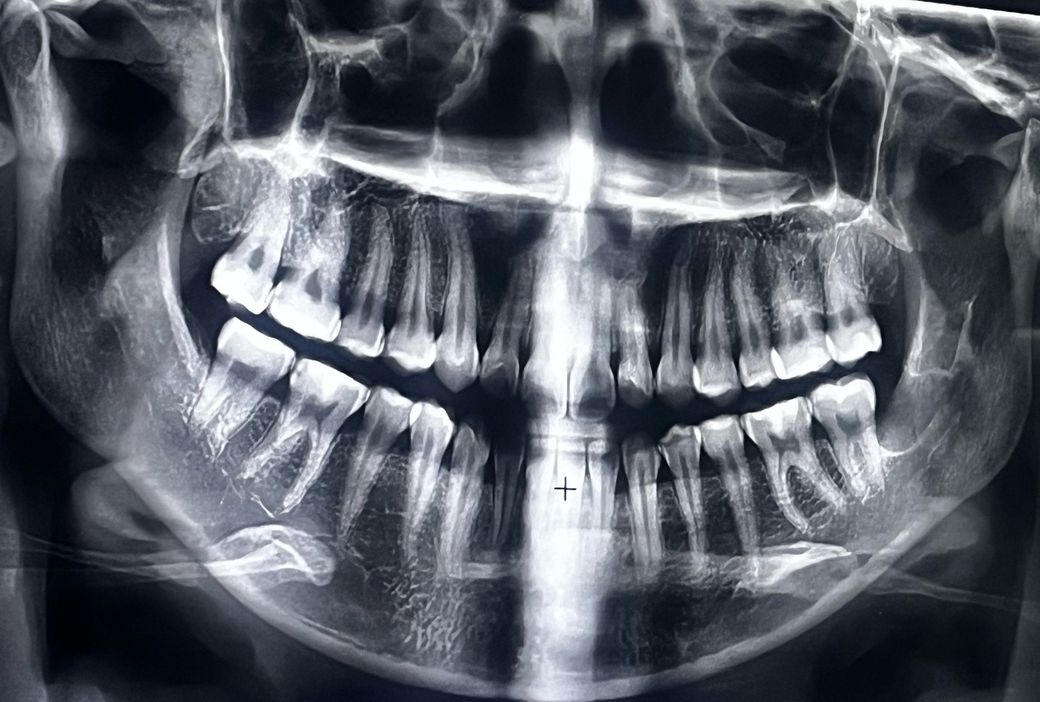

오른쪽 인접면 충치치료 진행상황 알러주세요

오른쪽 아래어금니쪽 인접면 충치가 있어서 인레이로 진행해야될 것 같다고 하셨습니다

(추가적으로 열어봤을때 너무 심하면 신경치료 고려해야한다고도 하셨습니다)

첫번째 사진은 최근 사진이고

두번째 사진은 처음 간 병원에서 찍은 사진입니다

(사진찍고 사랑니 발치 후 , 왼쪽 오른쪽 윗 어금니 • 왼쪽 아래어금니 레진치료 했습니다)

첫번째 사진에서 왼쪽 아래 뒤쪽 치아사이에 인접면 충치가 잇는거 같습니다. 치료를 하셔야될것같습니다.

오른쪽 아래 여섯 번째와 일곱 번째 어금니 사이에는 인접면 충치가 있는 것이 맞습니다. 인접면 충치가 있는 경우에는 레진으로 충전을 했을 경우 경계면을 만들어주기 힘들기 때문에 보통 인레이 치료를 하게 됩니다.